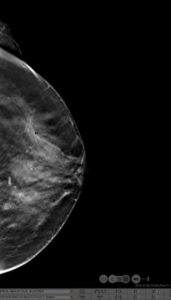

39yr old lady with history of lump in the left breast UIQ, No previous imaging done. No positive family history for CA Breast/Ovary. Pre-Menopausal Status.

Mammography- Fairly well circumscribed predominantly sold lesion in the left breast UIQ with partially obscured margins. No spiculations. No associated microcalcifications noted. Sonography: Well defined hypoechoiec lesion with smooth margins.

Low-grade Mucinous Carcinoma ER?PR- +ve HER-2 NEU -VE